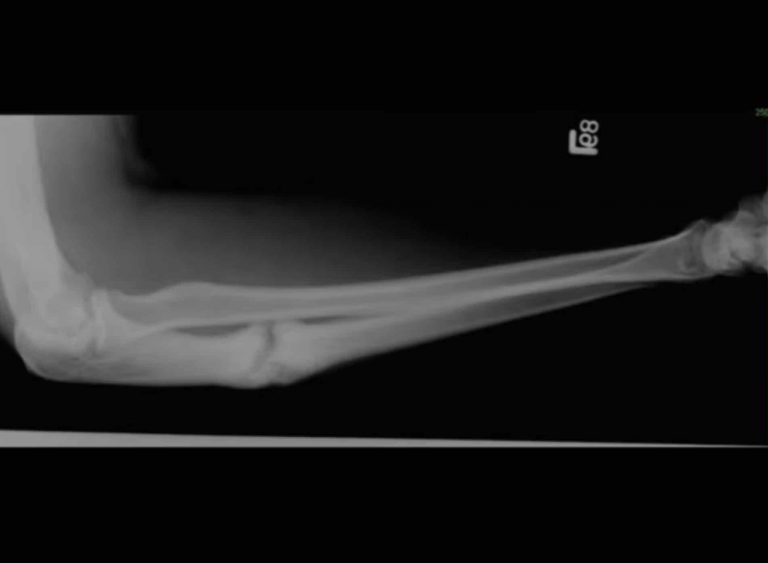

שבר באולנה

שבר באולנה (בעברית – עצם האמה), אחת משתי העצמות שבין המרפק לכף היד, מופיע בדר״כ קרוב למרפק. כשרופאים כותבים בשליש הפרוקסימלי הכוונה פרוקסימלי (״קרוב״) למרפק.

לאורך האמה שתי עצמות: הרדיוס והאולנה. הרדיוס נמצא ב"צד של האגודל "של הזרוע, והאולנה נמצאת ב"צד הזרת".

התסמינים כוללים כאב, עיוות, נפיחות, דימום תת עורי, הגבלה בתנועה וחוסר תחושה או חולשה באצבעות או בשורש כף היד. כמובן שרק צילום רנטגן יאמת את החשש.